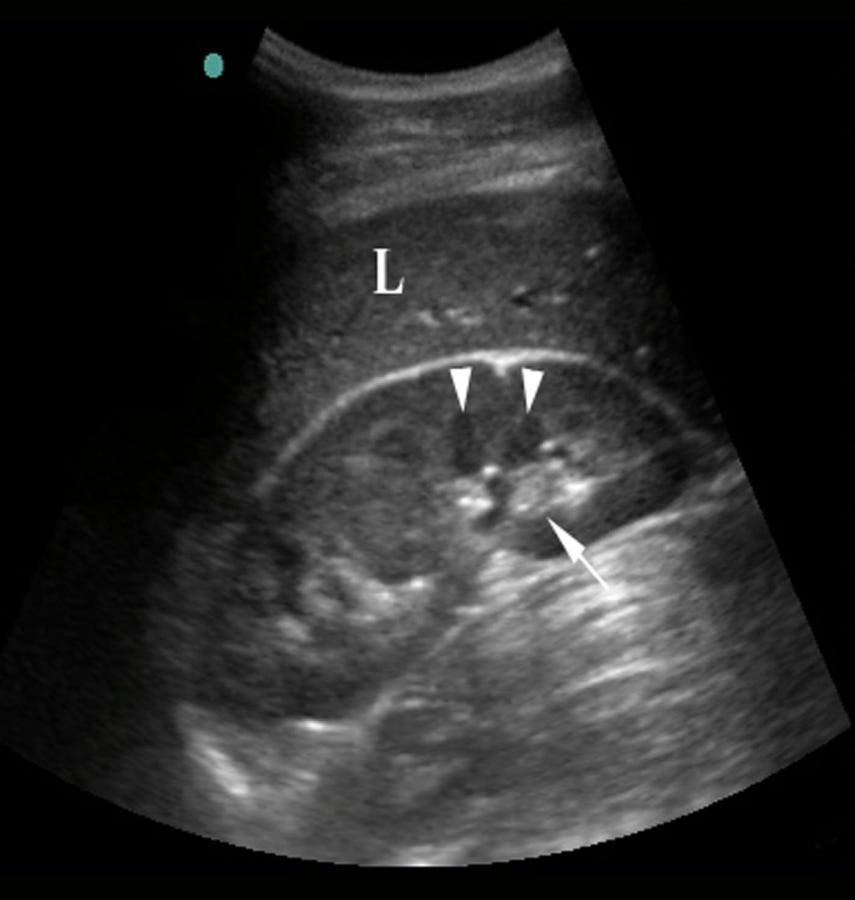

Femur length (FL) dimension. Fig. 5 Abdominal circumference (AC What Is Fl Means In Ultrasound Femur length is a marker for fetal growth and health, measured in millimeters on ultrasound. Learn how to measure fetal biometry parameters such as bpd, hc, ac, fl, and others from 14 to 40 weeks gestation. It is also called intrauterine growth restriction (iugr). It measures the diameter of your baby's. All eligible pregnancies underwent ultrasound evaluations for estimated fetal. What Is Fl Means In Ultrasound.